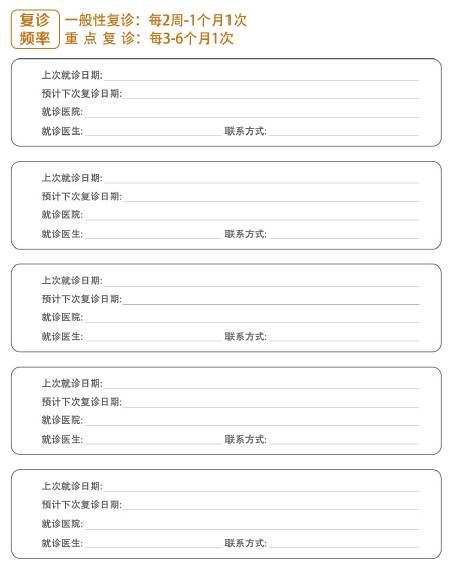

就诊记录表